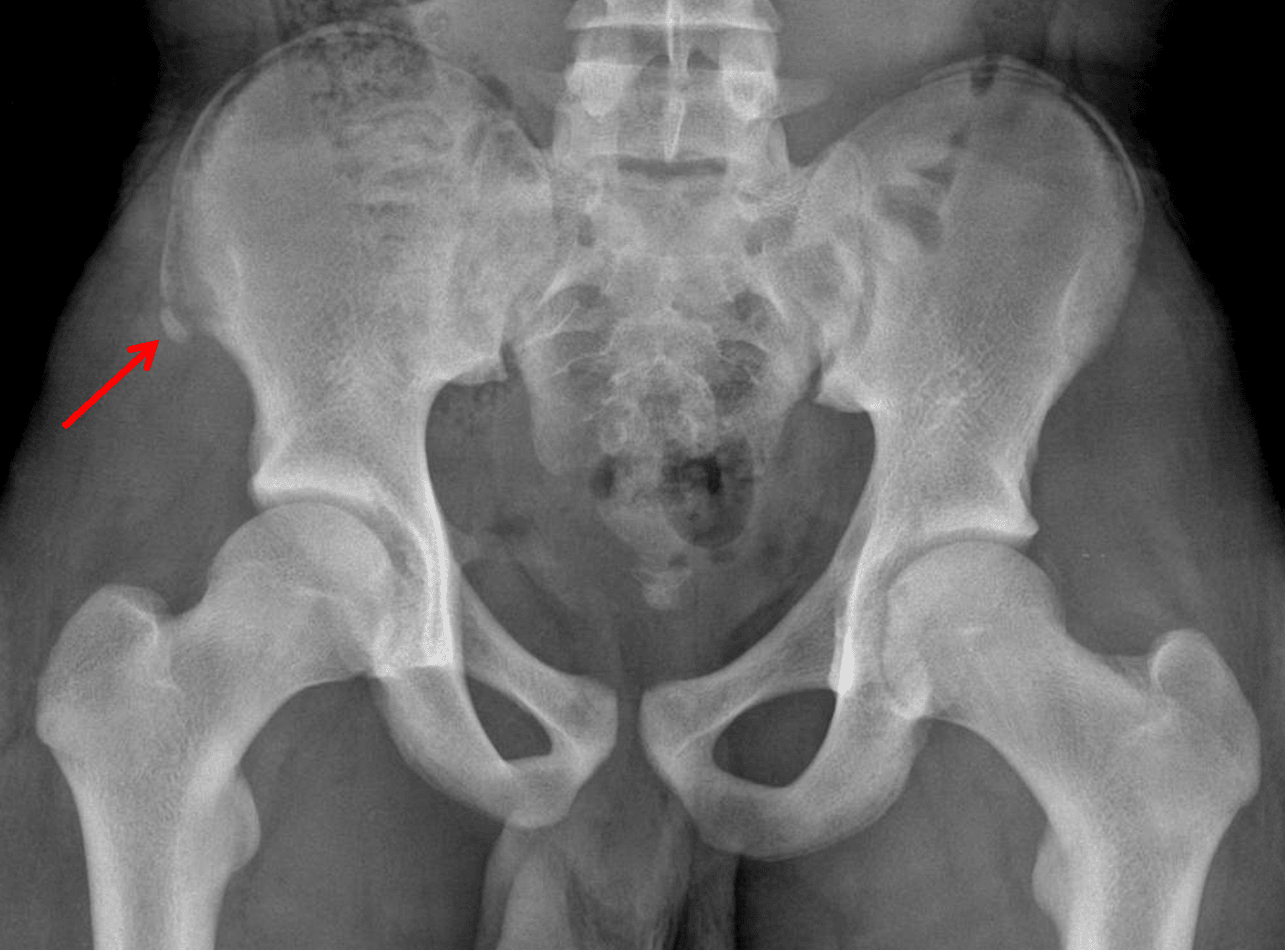

Findings

- Acute avulsion fracture of the right anterior superior iliac spine

Sample Report

Acute avulsion fracture of the right anterior superior iliac spine (ASIS).

No joint malalignment.

Red arrow: ASIS avulsion fracture in this patient.